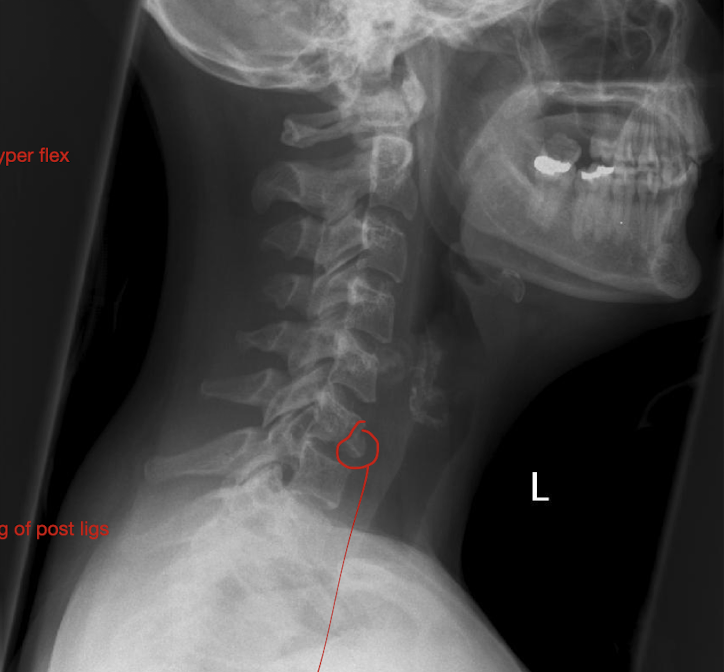

Fracture of C3-C7: Tear Drop Fx

What is this fx known as?

How does it occur?

2

Known as:

Most severe of the Lower C/S Fx (Hyper Flexion)

How:

Separation of a piece of bone from the Anterioinferior border of the vertebral border

Hyperflexion or Hyperextension

Fracture of C3-C7: Tear Drop Fx

How much force causes pieces to rupture off and tearing of post ligs.

Stable or Unstable Injury

Large Force

Unstabble